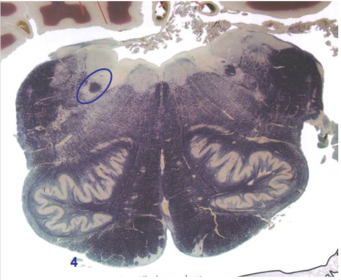

| Nucleus gracilis | |

| Nucleus cuneatus | |

| Fasciculus gracilis | |

| Fasciculus cuneatus | |

| Internal acruate fibers | |

| Lateral (external/accessory) cuneate nucleus | |

| Medullary pyramids | |

| Hypoglossal nucleus | |

| Hypoglossal nerve | |

| Dorsal motor nucleus of X | |

| Nucleus ambiguus | |

| Solitary tract | |

| Solitary nucleus | |

| ALS | |

| Medial lemniscus | |

| Medial longitudinal fasciculus | |

| Spinal tract of V | |

| Spinal nucleus of V | |

| Lateral (external, accessory) cuneate nucleus | |